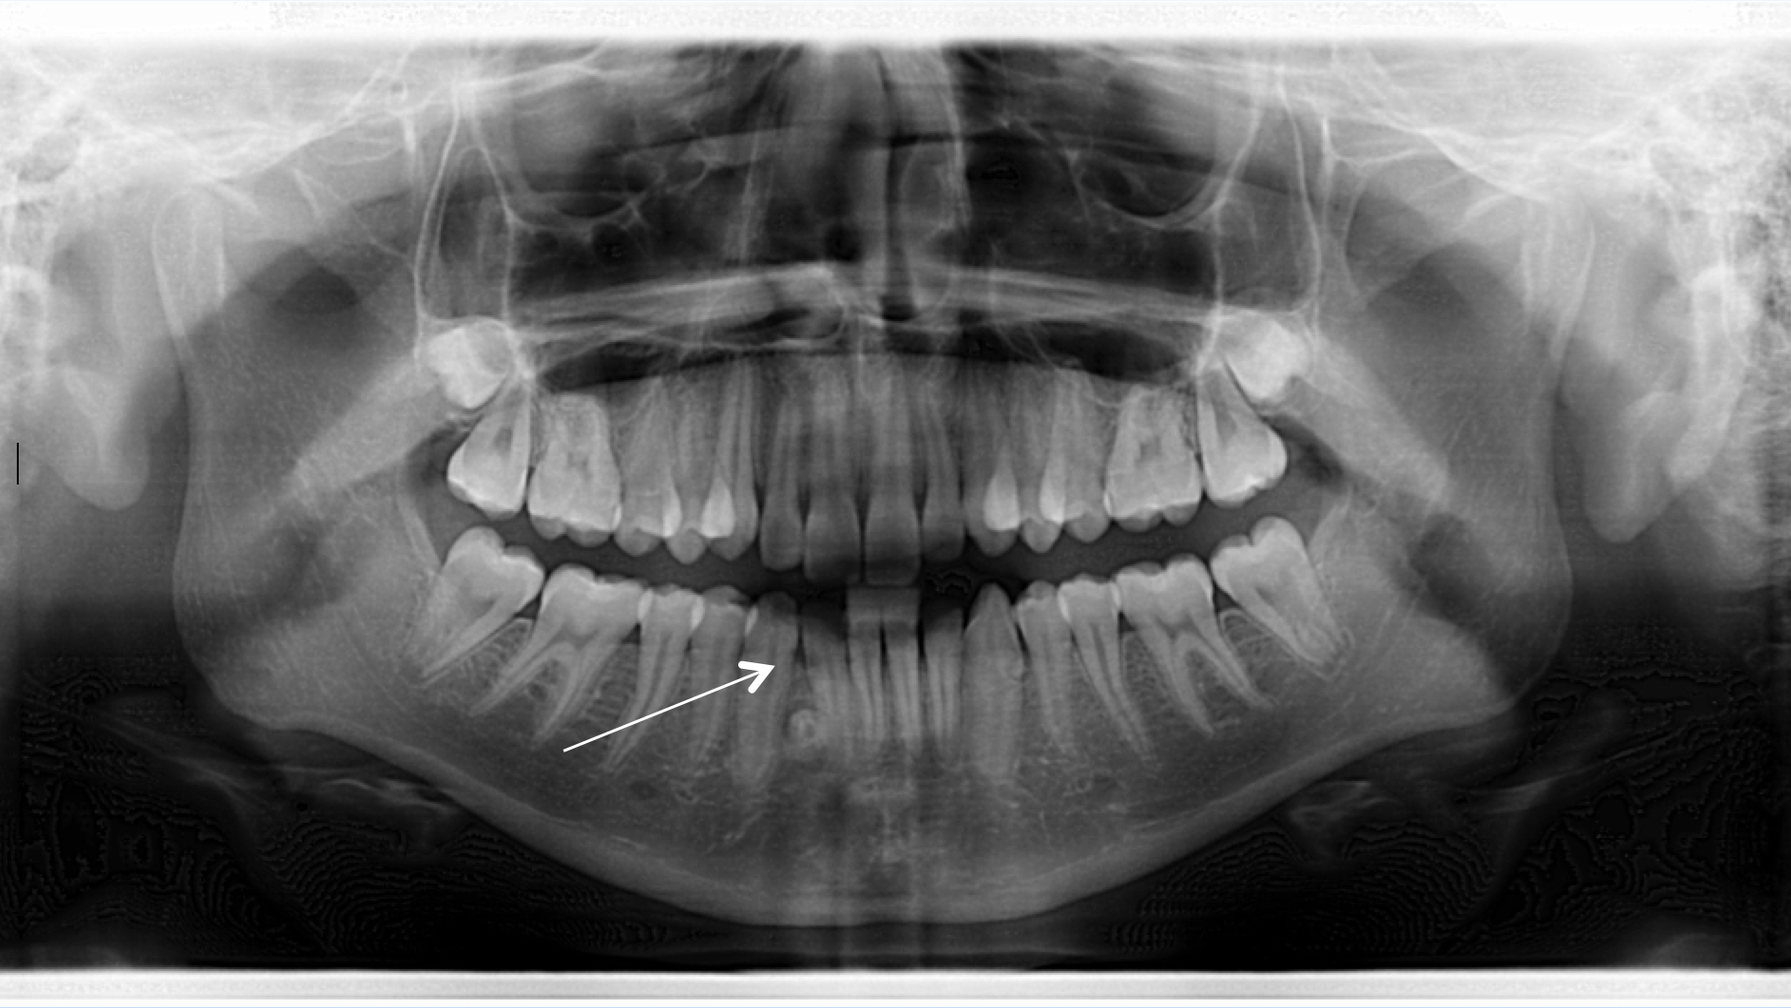

A healthy 14-year-old female presents to the office for a comprehensive exam prior to her getting braces. A panoramic radiograph revealed congenitally missing teeth (nos. 17 and 32). In between the lower one-third root apices of nos. 26 and 27, a circular radiopaque lesion was noted. It measured approximately 5 mm in diameter. Intraorally, the area was not tender to palpation, and both the patient and her parents were unaware of its presence.

Diagnosis

Odontoma. An odontoma is a benign tumor containing a cluster of all the various component tissues of teeth.1 It compromises 67% of all odontogenic tumors.1 Odontomas will typically form in tandem with natural dentition. Most odontomas do not present with any signs or symptoms; however, depending on their location, they can hinder or delay the eruption of the permanent teeth.1 Odontomas occur more frequently in the maxilla, usually in the anterior part of the mouth, either over the crowns of unerupted teeth or between the roots of erupted ones.2 Lesions appear as a radiopaque mass, are usually well encapsulated, and can be easily removed without complication.1,2